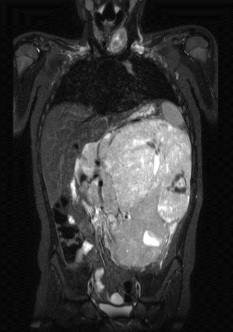

5. RMN Abdomen con contraste:

RMN: Masa retroperitoneal hipointensa en T1, realce heterogéneo con el contraste.

Hiperintensa en T2. Restringe en su mayor proporción y áreas que no restringen en relación

con áreas de necrosis.